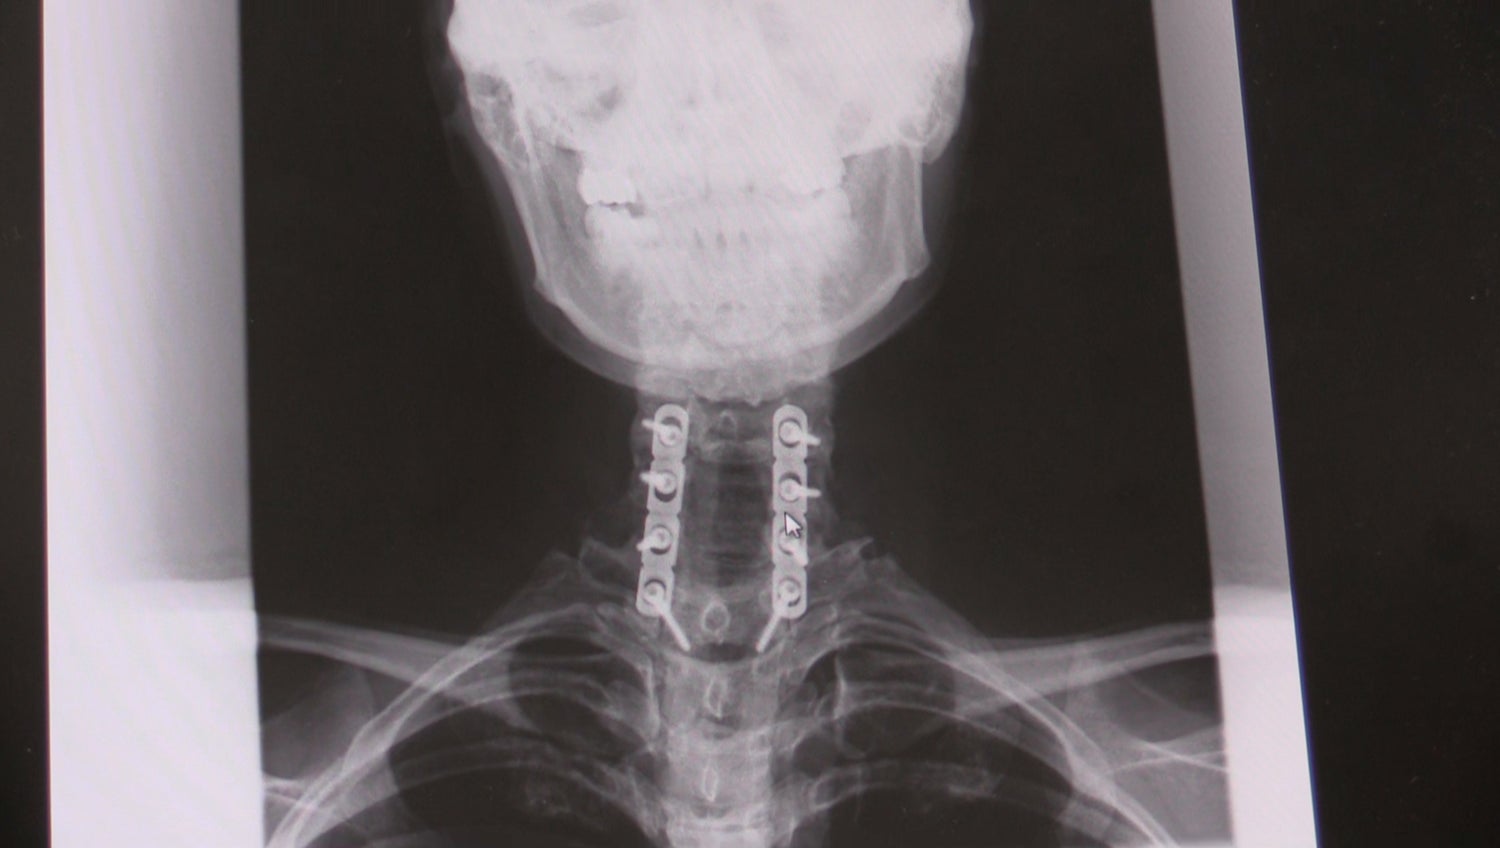

2002年NYの美大を卒業したばかりの“私”は、交通事故で脊髄損傷という大怪我を負い、突然それまでの日常を失った。